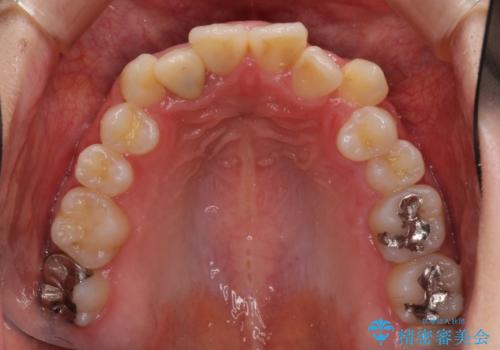

- 上下のデコボコと奥歯の咬みにくさを気にして来院された患者様です。

上顎骨の幅が下顎骨よりも小さいので、拡大装置により骨幅を広げて上下関係を改善し、その後インビザラインにて歯並びを整えることとしました。